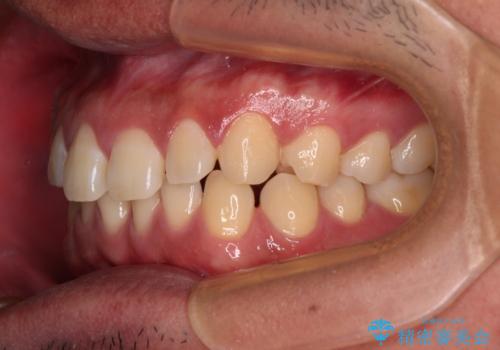

- 上下前歯の隙間を気にして来院された患者様です。

飲み込みや話をするときに舌を突出させる癖が強くあり、それが原因でスペースが空いていました。

舌のトレーニングをしっかりと行ってくださったおかげで、順調に治療を終えることができました。

舌の突出癖が速やかに改善され、後戻りによるスペースは今のところ認められておりません。